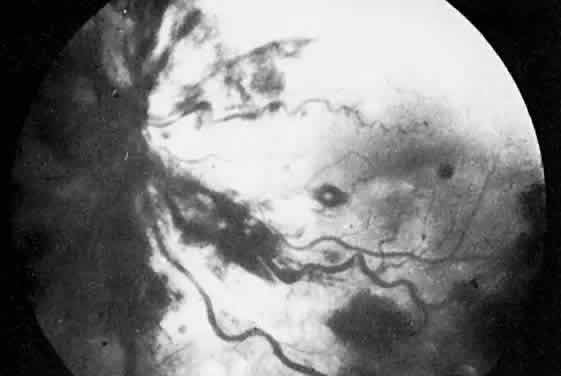

The most common ocular manifestations of TTP include papilledema, extraocular muscle palsies, and visual field defects, which usually are secondary to concomitant CNS involvement.75 Retinal findings consist of hemorrhages, retinal vascular occlusions, and serous detachments76,77 (Figs. 8 to 10). The cause of the serous detachments appears to be focal occlusion of the choriocapillaris resulting in retinal pigment epithelial damage and blood-retinal barrier disruption.76,77 Findings on fluorescein angiography are characterized by focal areas of nonperfusion of the choriocapillaris associated with late leakage into the subretinal space76 (Fig. 11). This is consistent with histopathologic studies that show occlusion of the choriocapillaris and large choroidal vessels, presumably by fibrin, with overlying necrosis of thepigment epithelium.75,76 TTP also has been linked in one case report with Purtscher retinopathy.78

Fig. 11. Fluorescein angiogram of patient with thrombotic thrombocyto-penic purpura showing late choroidalhyperfluorescence caused by focal areas of choriocapillaris nonperfusion. (Courtesy of Jerry Neuwirth, MD.)

Clinically, the development of serous retinal detachments usually is associated with exacerbations of TTP and the development of acute hypertension. Although serous retinal detachments have been described as a preterminal event, resolution of the detachments with subsequent pigment epithelial changes may occur when the underlying hypertension and thrombocytopenia are controlled.77